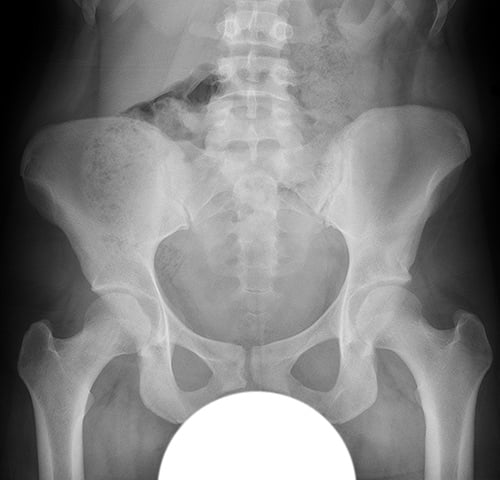

In surgical hip dislocation, the ball or head of the femur is separated out from its normal position of rest in the acetabulum. [Figure 1]

Figure 1. Anterior-to-posterior (front-to-back) X-ray image of the pelvis showing both hips. The ball of each femur rests in the acetabulum.